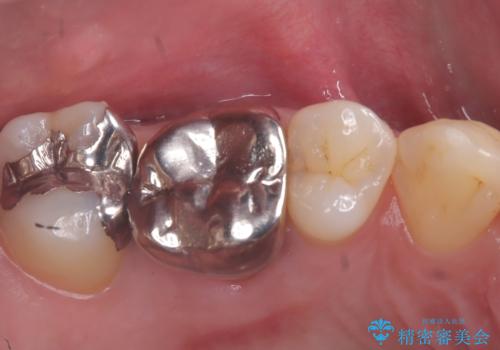

- 主訴:銀歯の入っている歯の側面に穴が空いている気がする。そこに食べ物が詰まる。

右上6番目の歯の被せものと歯質の境目に大きな窪みが出来ており、そこに汚れが停滞しやすい状態で虫歯もそこから広がっていたため、被せもののやり替えと必要に応じて土台の立て直しも行うこととしました。